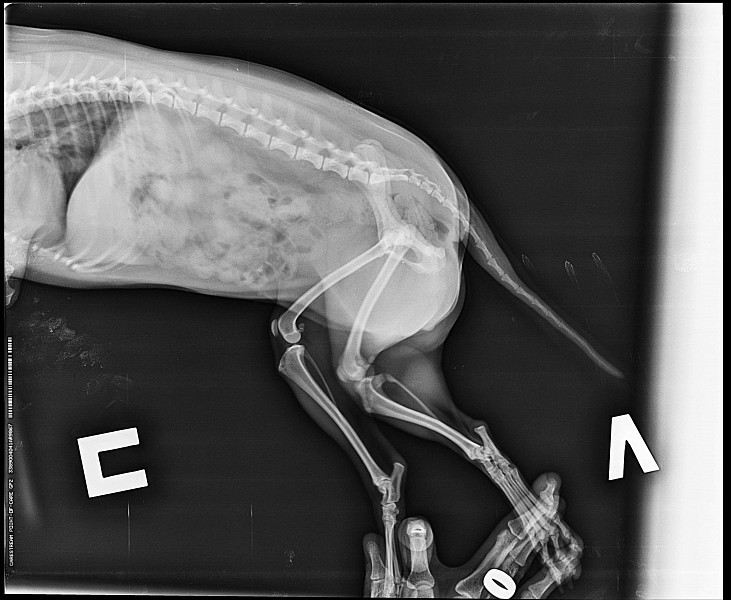

Рентген Задней Лапы Кошки: Нормы и Диагностика